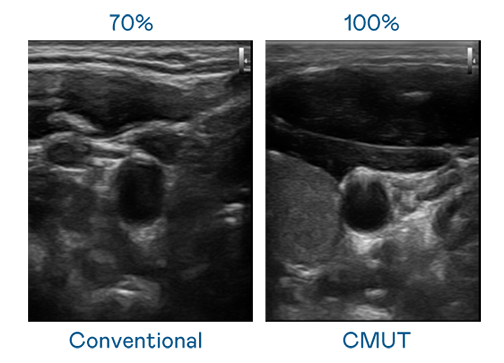

CMUT 技术是一种用电容式微机电元件来产生超音波讯号的技术。与传统 PZT 压电式技术相比,CMUT 频宽增加 30%,更宽频的超音波讯号让影像解析度大幅提升,是实现高影像品质医疗超音波扫描、促进精准医疗发展的关键技术。

大频宽带来超清晰影像

超音波影像的解析度高低,首先取决于探头能发出的讯号频宽。BC贷 CMUT 可提供高清晰的超音波讯号,提供高频宽、高灵敏度、影像纹理细节更高的超音波影像,协助医护人员缩短影像判读时间及利用精准的医疗影像进行诊断。